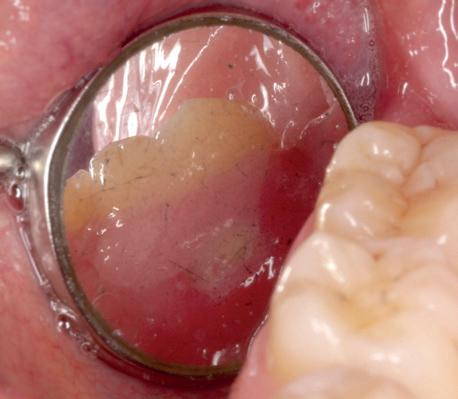

Zes maanden na extractie wordt het implantaat 37 geplaatst. Er is sprake van een goede genezing en de processushoogte en -breedte zijn behouden en opgebouwd. Ook is er zichtbaar gekeratiniseerd weefsel

1 2 Ridge preservation met d-PTFE membranen 35

gewonnen. De wond kan na het plaatsen van een healing abutment primair gesloten worden (Afbeelding 3a-3d).

In afbeeldingen 4a-c is het resultaat drie maanden na het plaatsen van het implantaat te zien. De genezing is volledig en de verwijzer kan de suprastructuur vervaardigen (afbeelding 4a-4c).